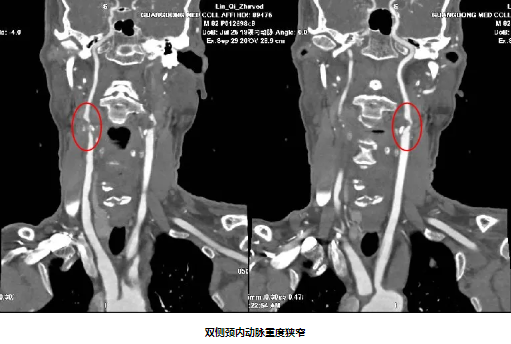

82岁男性,因“双下肢无力10天”入院,既往有“高血压病”史10年。入院后完善颈动脉彩超及影像学检查提示:1.分水岭梗死(双侧皮质下型)2.双侧颈内动脉重度狭窄 3.窦性心动过缓。经颈动脉狭窄MDT团队充分讨论,精心安排,在心血管内科中心的协助下,脑血管病专科团队克服了患者高龄、心动过缓等危险因素,成功给予患者双侧颈动脉支架同期植入,患者症状得到明显好转。